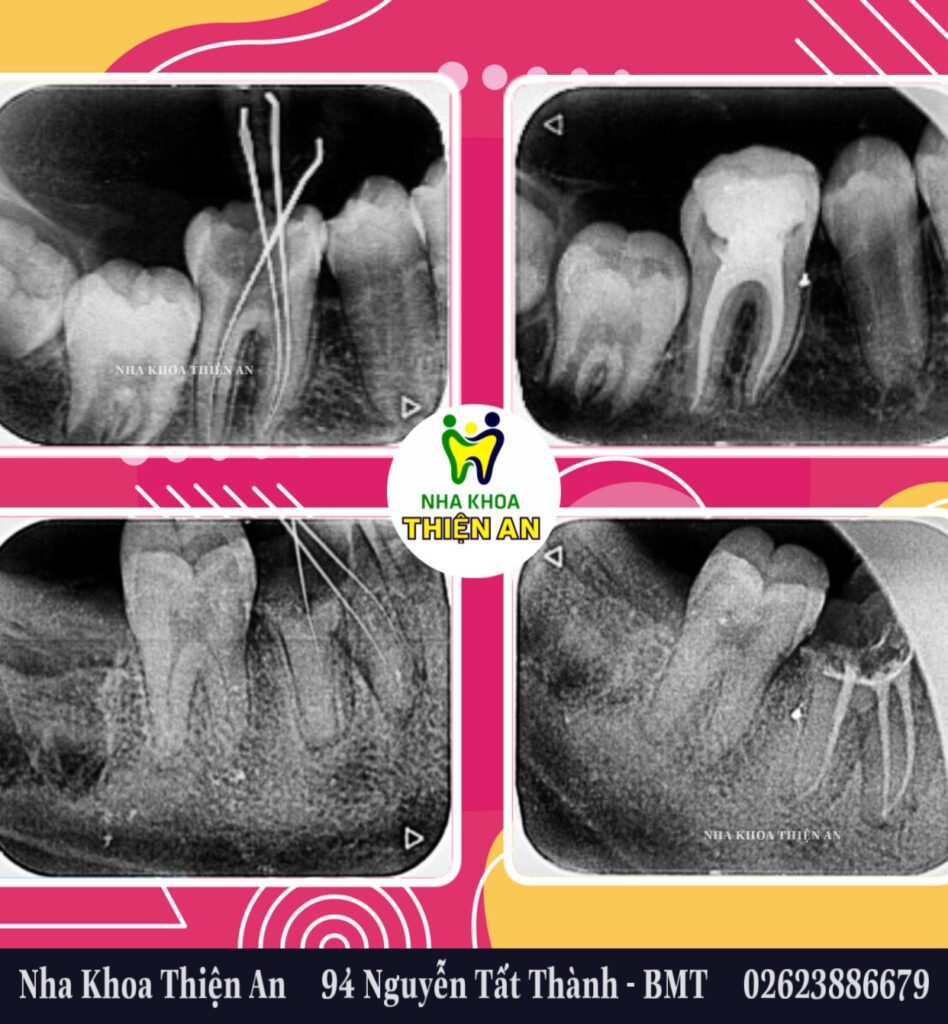

Điều trị tủy bằng máy nội nha tại nha khoa Thiện An BMT – Đăk Lăk giúp lấy sạch phần tủy hỏng tốt hơn, rút ngắn thời gian điều trị, xử lý được ống tủy cong….. giúp cho việc thành công sau điều trị tủy

Root canal treatment with an endodontic machine at Thien An BMT Dental Clinic – Dak Lak helps clean out damaged pulp better, shortens treatment time, handles curved root canals…. helping to achieve success after treatment. Root canal treatment

tại nha khoa Thiện An BMT – Đăk Lăk, 94 Nguyễn Tất Thành (đối diện Bitis)

- BS. CK2 Huỳnh Thanh Trung– Giám đốc Nha Khoa Thiện An, Nguyên Trưởng Khoa Răng Hàm Mặt, BVĐK Vùng Tây Nguyên

- ThS.Bs Nguyễn Thị Bích Ngọc, Nguyên Giảng viên Khoa Y Dược, Trường Đại Học Tây Nguyên trực tiếp điều trị.

at Thien An Dental Clinic BMT – Dak Lak, 94 Nguyen Tat Thanh (opposite Bitis)

- BS. CK2 Huynh Thanh Trung- Director of Thien An Dental Clinic, Former Head of Odonto-Stomatology Department, Central Highlands General Hospital

- Mrs.Dr Nguyen Thi Bich Ngoc, Former Lecturer of Faculty of Medicine and Pharmacy, Central Highlands University directly treated.